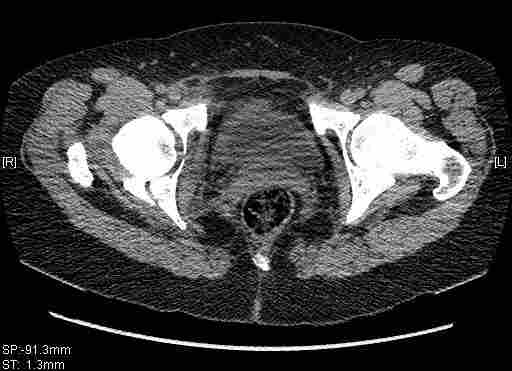

Женщина,58 лет, после ДТП 6 суток. Первично повреждение расценено как переломы ветвей лонной кости. После подтверждения повреждения вертлужной впадины,как чаще всего случается, вопрос встал о тактике. БОльшинство за консерватиное лечение.К сожалению кт у нас "во время" сломался. Прилагаю стандартные снимки вертлужки. У меня следующие вопросы к коллегам:1. Правильно ли рассценивать это повреждение как Т-образный перелом вертлужнй впадины?2. Можно ли добиться анатомической репозиции поверхности вертлужной впадины скелетным вытяжением в данном случае, если нет, что будет этому препятствовать?3. Если смещение останется таким как сейчас, через какое время появится необходимость эндопротезирования (по вашему опыту)?Спасибо.

Удалось сегодня вывести пациентку в соседнюю больницу, где есть кт. Срезы сделаны только горизонтальные.

|